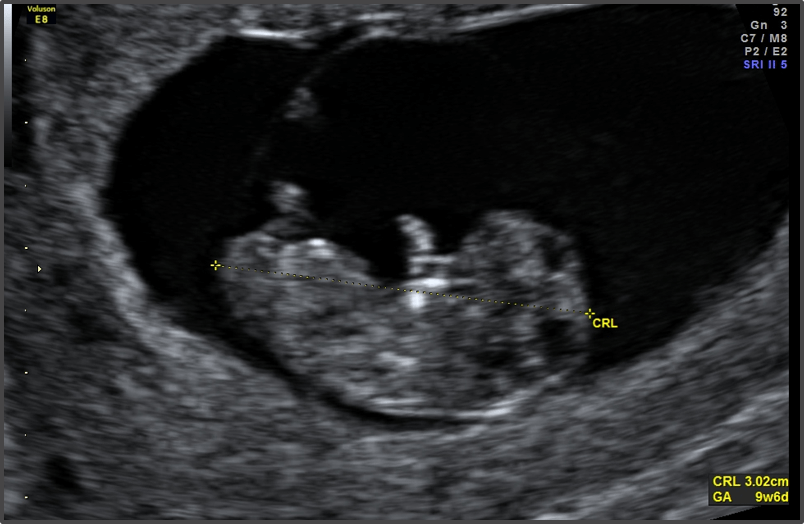

The baby's major organs are starting to form.

Baby is the size of Olive

Approx Baby Weight: 2g

Approx Baby Size: 2.3 cm

The heart is fully formed and pumping blood.